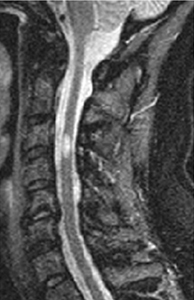

ზურგის ტვინის მაგნიტურ რეზონანსული ტომოგრაფია რეკომენდებულია ყველა პაციენტისთვის, გაფანტული სკლეროზით დაავადებულ ბევრ პაციენტს აქვს ზურგის ტვინის კისრის წილის დაზიანებები. ამ ნიშნის სპეციფიკურობა ძალიან მაღალია.[Figure caption and citation for the preceding image starts]: ხერხემლის კისრის ნაწილის მაგნიტურ-რეზონანსული ტომოგრაფია მაგნიტური ველის მაღალი სიმძლავრით(1≥ ტესლა) ასახავს დაზიანებს, რომელიც შესაძლოა იწვევდეს ნაწლავებისა და შარდის ბუშტის დისფუნქციის, ასევე სპასტიური პარაპარეზის მიელოპათიურ სიმპტომებს.From the collection of Dr Lael A. Stone [Citation ends].

საჭიროა კისრის და გულმკერდის/წელის სეგმენტების ვიზუალიზაცია, მოიცავს კონუსსაც. შეიძლება გამოიყენოთ 1.5 T ან 3 T სკანერი. მიზანშეწონილია გამოიყენოთ საგიტალური გადოლინიუმით გაძლიერების მოდული.[3] მაგნიტურ რეზონანსული ტომოგრაფია ასევე გამოიყენება დაავადების აქტივობის შესაფასებლად და მკურნალობის ეფექტურობის მონიტორინგისთვის.[3]